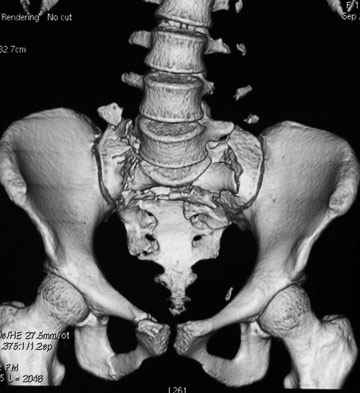

Травма 21.августа 2005г. На девочку в лесу упала береза. Доставлена в ближайшую ЦРБ. При поступлении установлен диагноз: Травматический шок 2-3 ст. Тупая травма живота. Забрюшинная гематома. Перелом костей таза с нарушением целостности тазового кольца. Перелом лонной и седалищной костей справа. Перелом поперечных отростков L3 - L5. Разрыв КПС справа. При поступлении выполнена диагностическая лапароскопия — выявлена обширная забрюшинная гематома. Было наложено скелетное вытяжение за бугристости обеих б/берцовых костей, больная уложена в гамак. Через неделю скелетное вытяжение демонтировано, гамак снят. Девочка уложена в положение «лягушки». Контрольные рентгенограммы через 4 недели после травмы. Заподозрен перелом дужки L5. Больная 26 сентября 2005 г. переведена в областную больницу в отделение детской ортопедии. При поступлении в локальном статусе: пальпация и перкуссия остистых и поперечных отростков L4-5 болезненная. Пальпация костей таза б/болезненная. С-м натяжения слабо положителен. Осевая нагрузка положительная. Движения в т/б суставах ограничены, болезненны. C-м прилипшей пятки отрицательный. C-м Ларрея и Варнейля отрицательный. Периферическая гемодинамика не нарушена.Неврологический статус: вторичная двусторонняя радикулопатия L5-S1. 29 сентября произведена компьютерная томография позвоночника и таза.

Судя по томограммам, радикулопатия может быть из-за компресии "конского хвоста" смещенным крестцовым позвонком, это хорошо видно на втором слева снимке. Если этот сегмент будет нестабилен и будет сохраняться неврологическая симптоматика, придется оперировать. Если неврологическая симптоматика уйдет и перелом стабилизируется, то можно обойтись без операции.